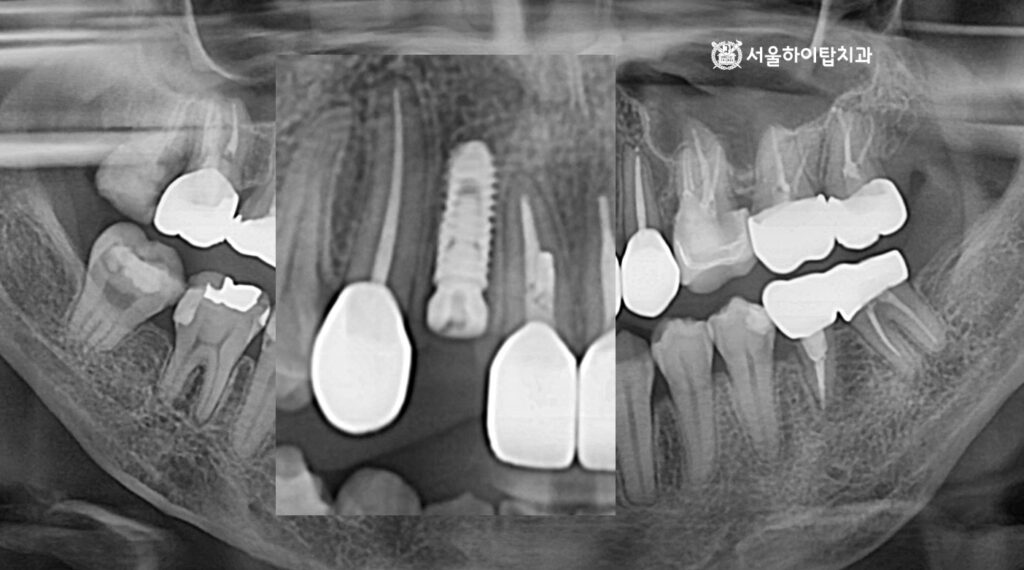

최종 보철 – 지르코니아 크라운 장착

앞서 진행한 쉐이드 체크를 통해 주변 자연치와 조화롭게 어울리는 색상을 선택되었으며,

이 데이터를 바탕으로 최종 지르코니아 크라운을 제작하여 장착한 모습입니다.

파노라마 엑스레이에서도, 픽스처가 골 속에 단단히 심겨져

안정적인 모습을 확인할 수 있으며,

주변 치아와도 조화로운 배열을 이루고 있음을 확인할 수 있습니다.